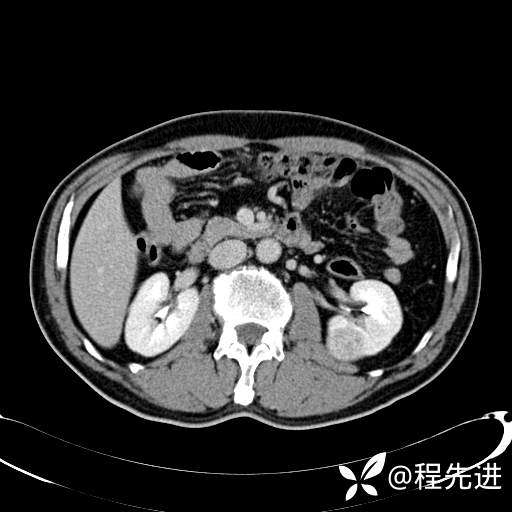

患者性别:男

患者年龄:65岁

简要病史:腰痛2月,体检发现左肾占位5天

皮质期: